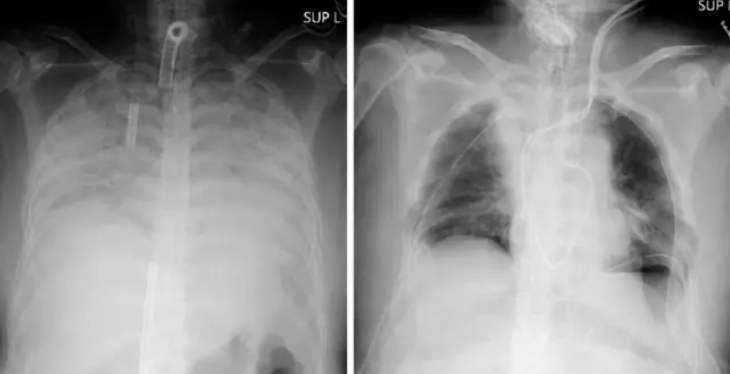

Japonke nakazenej Covidom-19 lekári transplantovali pľúca od živých darcov a je to prvý prípad na svete

V Japonsku zaznamenali vôbec prvý prípad na svete, kedy žijúca osoba darovala časť svojich pľúc na transplantáciu. Pľúca istej ženy boli koronavírusom vážne poškodené a podstúpila 11-hodinovú operáciu, počas ktorej dostala fungujúce časti pľúc.

Tento chirurgický zákrok uskutočnili vo fakultnej nemocnici Kjóto a podieľal sa na ňom tím 30 lekárov. Žene transplantovali pľúcne tkanivo od jej manžela aj syna. Obaja muži boli po operácii v stabilizovanom stave. Manžel daroval časť svojich pľúc z ľavej strany a syn sa vzdal časti pľúc z pravej strany.

Po úspešnej operácii hrudný chirurg Hiroshi Date, ktorý viedol celú operáciu povedal toto: „Ukázali sme, že je možné transplantovať pľúca, a to aj od živých darcov. Táto operácia je liečbou, ktorá dáva nádej ľuďom, ktorí kvôli Covidu-19 utrpeli vážne poškodenie pľúc“. Je to tak prvá transplantácia pľúc, na ktorej sa podieľali živí darcovia.

Koronavírus je nebezpečný aj kvôli tomu, že na niektorých ľudí má dlhotrvajúce a veľmi nepríjemné účinky aj po tom, čo tento vírus prekonajú. Štúdia vykonaná v Číne ukázala, že až 76% ľudí z 1 700 majú najmenej jeden príznak aj mesiace po infikovaní sa vírusom.

Foto: Facebook